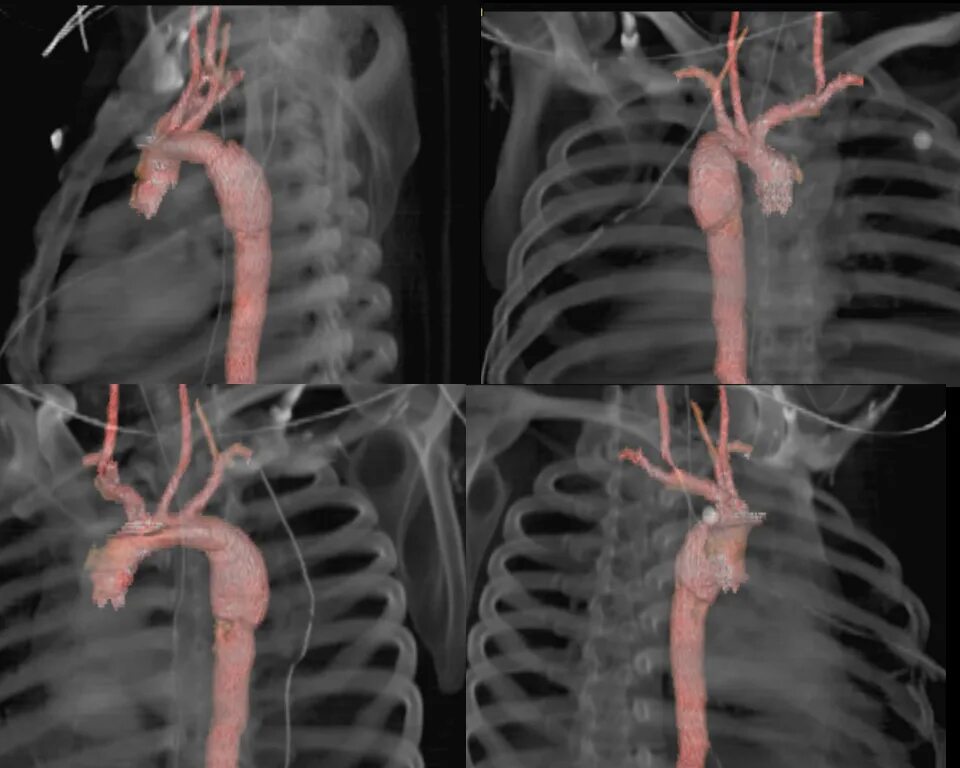

От чего бывает разрыв аорты